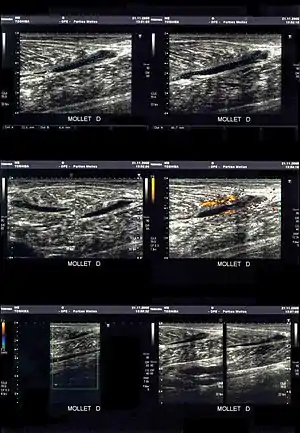

کشیدگی ماهیچهای

کشیدگی، بیشتر به علت نیروی کششی بیش از حد به بخش عضلانی-تاندونی ایجاد میگردد. گاهی انقباض شدید عضلهای که در برابر یک مقاومت بالا قرار میگیرد منجر به کشیدگی میگردد.

درجات کشیدگی ماهیچهای

کشیدگی ماهیچهای یا عضلانی، که به آن «استرین» هم میگویند، یک عامل مهم در ایجاد دردهای عضلانی است. بسیاری از دردهای ناحیه کمری به علت صدمات عضلانی یا لیگامانی (اسپرین) به وجود می آید. استرینها یا کشیدگیهای ناتوانکننده عضلانی اکثراً در عضلات بزرگی همانند همسترینگ و چهارسر رانی (کوادریسپس) در اندامهای تحتانی اتفاق میافتند[1].

شدت آسیب در کشیدگیهای عضلانی سه درجه دارد که عبارتنداز:

- درجه ۱: میزان آسیب و درد کم بوده و تورم ماهیچه خفیف است.

- درجه ۲: آسیب متوسط بوده و بنابراین درد و تورم وجود دارد. خونریزی بافتی ایجاد میشود.

- درجه۳: پارگی بافتی که همراه با خونریزی است. فرد درد شدیدی را در لحظه آسیب حس میکند. تاندون ماهیچه دوسر بازویی و تاندون آشیل دو محل شایع پارگی هستند.